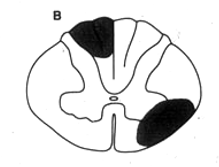

Subacute Degeneration of the cord